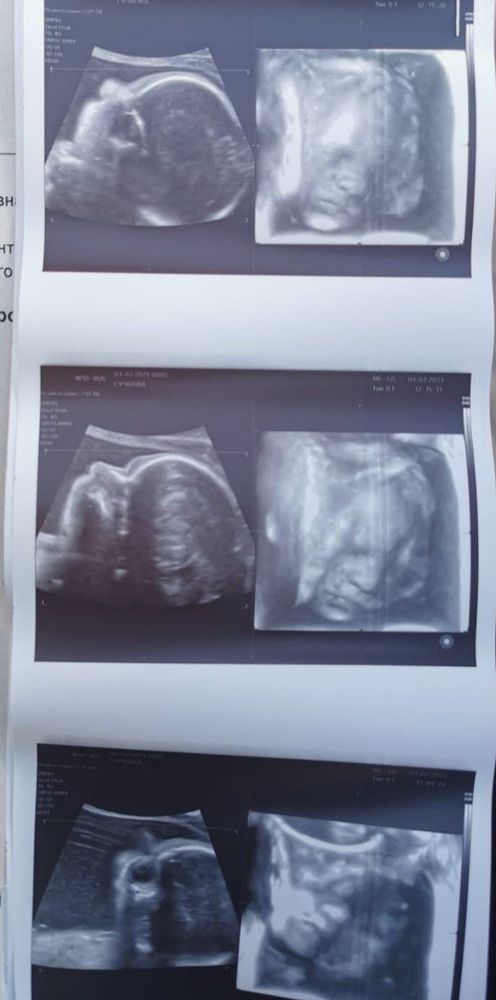

3д фото малыша

Изображение В 32 недели

Изображениес дочей в 25 недель ходила)